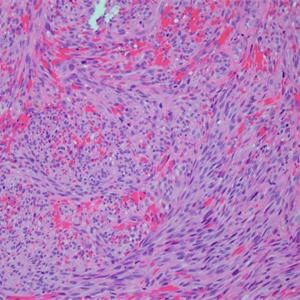

IV 期为结节期:结节期的病变边界清楚,主要由网状或裂隙状的毛细血管及其周围纵横交错的嗜酸性梭形细胞组成,梭形细胞有一定异型性,核分裂偶见;梭形细胞和血管之间为含有红细胞的裂隙,横切面呈筛孔状或蜂窝状,在梭形细胞内或细胞外可见抗淀粉酶消化 PAS 阳性的嗜伊红色透明小体,结节的边缘常见炎症细胞浸润、含铁血黄素沉着和扩张的血管。 典型的卡波西肉瘤细胞无明显的异型性,核分裂像也不多见,但少数病例中瘤细胞分化较差,异型性明显,可见较多的核分裂像。

- 银染见网状纤维分布于梭形细胞之间并围绕血管腔隙;